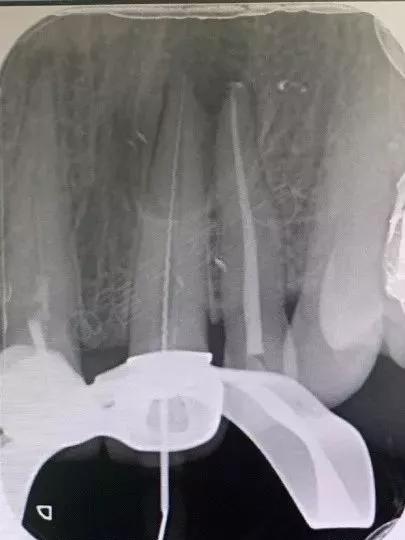

1.测量根管长度。通过X光、根管长度测量仪等工具确定根管的准确长度,以保证清洁时可以触及牙根内全部区域,达到最佳的清洁效果。

通过X光确认根管长度